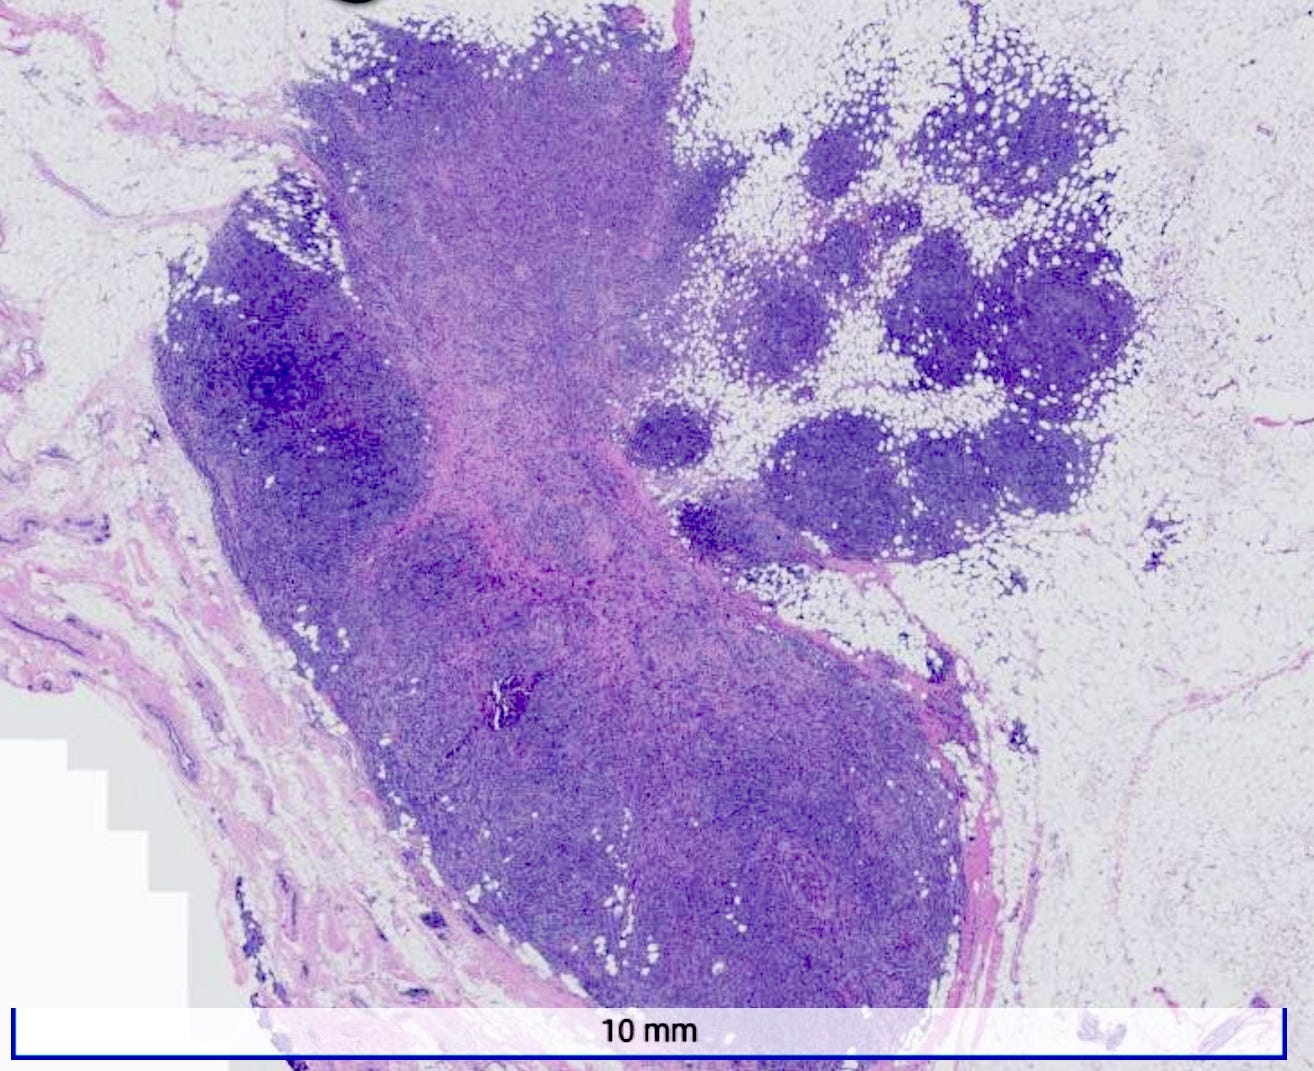

Medullary carcinoma of the breast is a rare subtype (3 - 5%) of invasive breast cancer with pushing borders, syncytial growth, high grade nuclei and a prominent lymphoid infiltrate. According to the World Health Organization, the preferred terminology is invasive breast carcinoma of no special type with medullary pattern.

Grossly, the tumors are usually 2 - 5 cm, well circumscribed, soft to firm, lobulated masses. Although they appear sharply demarcated from surrounding tissue, they lack a true capsule and may exhibit pushing, expansile borders without widespread stromal invasion.

Microscopically, medullary carcinoma is composed of large, pleomorphic, high grade tumor cells arranged in broad syncytial sheets occupying at least 75% of the tumor area. The tumor cells have vesicular nuclei (i.e., large, pale staining with a central clearing) with prominent nucleoli and abundant eosinophilic cytoplasm. A prominent and dense lymphoplasmacytic infiltrate surrounds and often infiltrates the tumor, suggesting a vigorous host immune response. Mitotic figures are numerous and areas of necrosis may be present.

Medullary carcinoma - radiologic and microscopic images